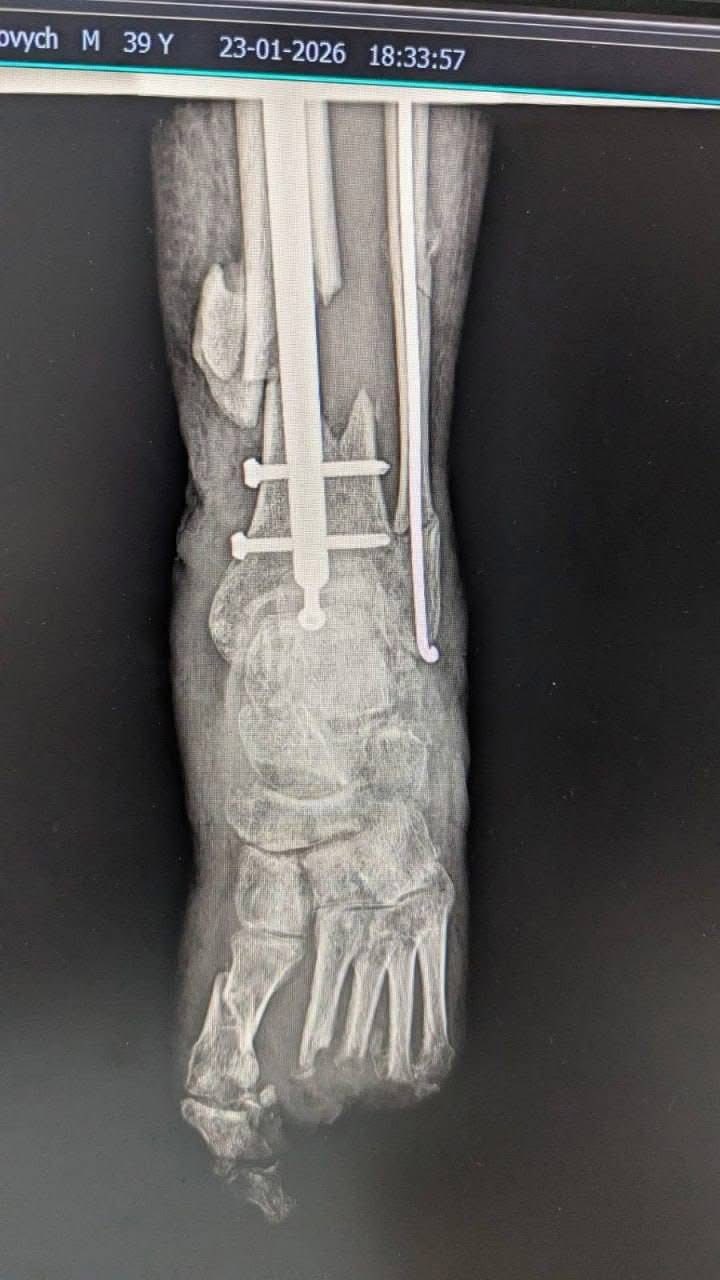

«Навіть під час повномасштабної війни українські медики не зупиняються: вони виконують складні реконструктивні операції, рятують життя та дарують нашим захисникам шанс знову жити повноцінно», — йдеться в дописі.